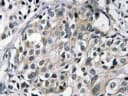

PolyclonalApplications: